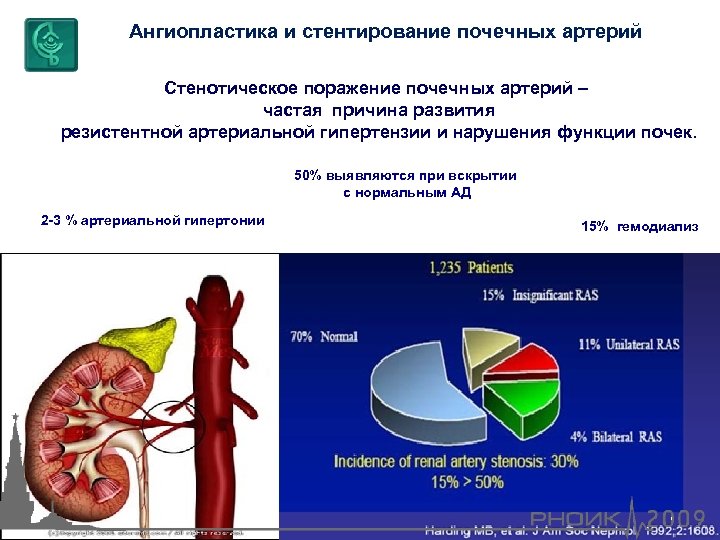

Ангиопластика и стентирование почечных артерий Стенотическое поражение почечных артерий – частая причина развития резистентной артериальной гипертензии и нарушения функции почек. 50% выявляются при вскрытии с нормальным АД 2 -3 % артериальной гипертонии 15% гемодиализ

Ангиопластика и стентирование почечных артерий Стенотическое поражение почечных артерий – частая причина развития резистентной артериальной гипертензии и нарушения функции почек. 50% выявляются при вскрытии с нормальным АД 2 -3 % артериальной гипертонии 15% гемодиализ